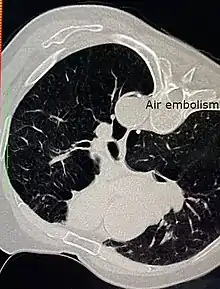

Air embolism

Air embolism in the descending thoracic aorta after CT guided percutaneous lung biopsy of a suspected lung tumour.